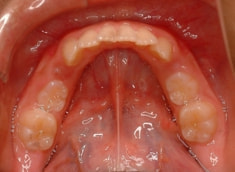

治療後(12ヶ月後)

外科矯正も回避できて、さらに非抜歯で本格矯正を行うことができると診断し、現在2期治療中です。

下顎前突症例によくある顕著な顔面非対称もなく、幅径も良好な状態です。

少し大臼歯の傾斜が認められます。

上顎8番は先天欠如、下顎8番は埋伏しております。

歯根のパラレリング(平行性)も悪くなく、上顎洞、顎関節にも異常所見はありません。